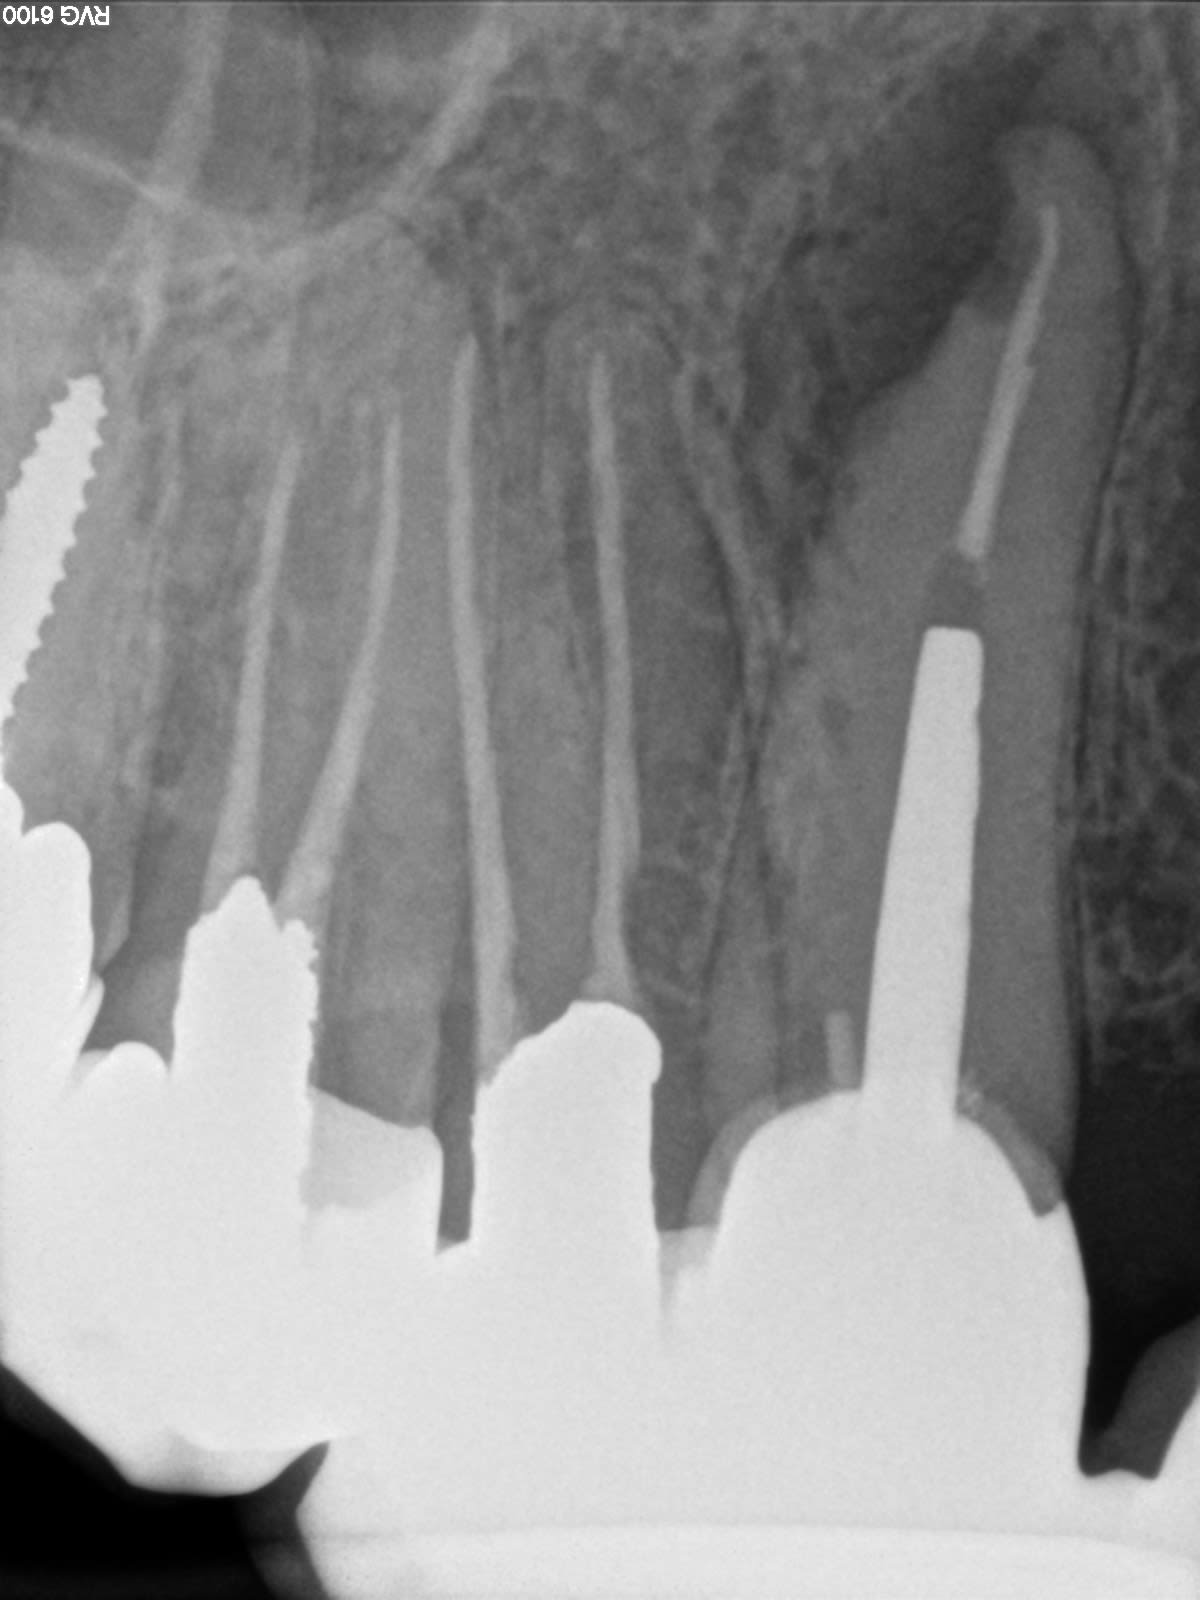

secteur 4, en 2005

secteur 3, en 2012

Pas de grande portée, mais ça tient, même si ça sent le sapin à droite